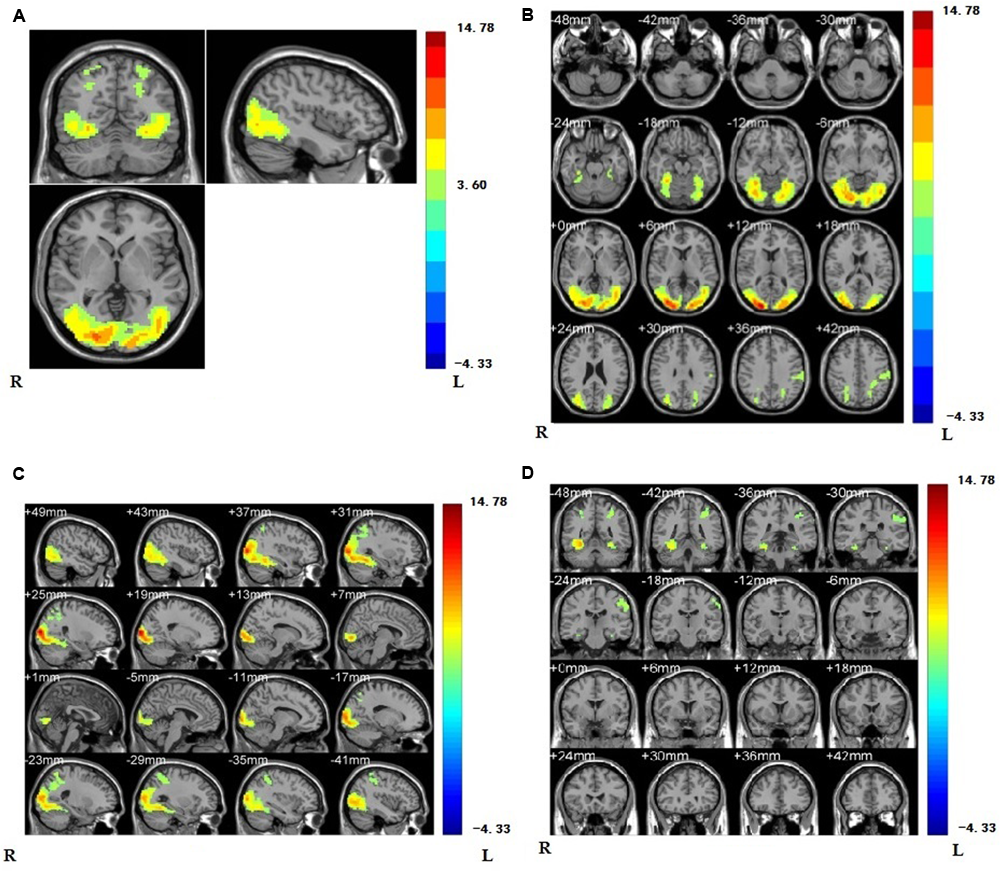

As a first step, we contrasted the brain activity of the painful conditions with the non-painful conditions for all the subjects. The results of (PVG + PNG) - (NVG + NNG) showed that when viewing others in pain, regions were activated in the right supramarginal gyrus (rSMG), lateral middle occipital gyrus, lateral fusiform gyrus, right inferior occipital gyrus, inferior parietal gyrus, middle temporal gyrus, and visual related regions such as V2 (see Figure 3 and Table 1).

FIGURE 3

(A) Regions showing higher activation are the regions of supramarginal gyrus, lateral middle occipital gyrus, lateral fusiform gyrus, right inferior occipital gyrus, inferior parietal gyrus, middle temporal gyrus, and visual related regions such as V2 compared with non-painful stimuli (p < 0.001, Alphasim corrected; k > 1361). We have separately MR imaging at the position of oblique-axial (B) plane, oblique coronal; (C) and sagittalia; (D) in regions activated.

Brain regions showing significant activation in lateral middle occipital gyrus, lateral fusiform gyrus, right inferior occipital gyrus, right supramarginal gyrus, inferior parietal gyrus, middle temporal gyrus, and visual related regions such as V2 while viewing painful stimuli compared with non-painful stimuli (p < 0.001, Alphasim corrected; k > 1361).